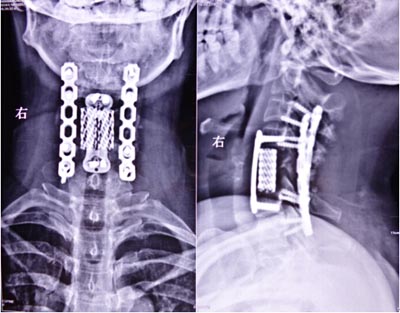

近日,我院骨二科成功完成一例前后联合入路颈椎肿瘤切除重建术。该患者来自陕西汉阴,女,45岁,1月前无明显诱因感颈肩部疼痛不适,在当地医院就诊行相关检查诊断:“颈5椎体病理性骨折”,考虑手术的风险及难度极高,建议转至我院。磁共振检查示“颈5椎体及附件破坏并塌陷”,椎动脉血管造影示“右侧椎动脉发育不良,颈5椎体及附加破坏并包绕椎动脉”。积极术前准备工作,全科讨论后制定前后联合入路肿瘤切除重建手术方案。手术于2014.10.20日如期进行,张晓琴教授负责麻醉,术中进行动脉血压监测、中心静脉压监测、动态血气分析、全面的的生命体征监测,确保了手术安全和平稳。手术由李浩鹏教授指导,王栋副教授主刀,赵波主治医师协助。先取颈部前侧入路,于气管鞘及食管鞘间隙进入,切除颈5椎体,术中可见颈5椎体破坏,彻底切除病变组织至双侧横突,显露椎动脉及神经根,小心完整切除右侧椎动脉包绕的鱼肉样病变组织,更换手套,取左侧髂骨修剪为颗粒状及短棒状置入钛网放置于颈5椎体缺损部,前方钛板固定进行重建。再取俯卧位,颈部后正中切口,彻底切除颈5棘突及双侧椎板至双侧横突,双侧侧块钢板固定。手术顺利,术前症状显著改善,术后第二天即可在颈托保护下下地活动。该部位解剖复杂,血管、神经多,不易分离,有可能损伤椎动脉,脊髓及神经根,引起截瘫、大出血,脑坏死等,风险很大。术中以最精准的操作,解剖性、根治性切除病灶,同时进行了骨性重建,保证了颈椎的稳定性。该肿瘤的成功切除及重建,显现了我院骨二科的综合技术实力,以及团结协作、严谨求实、不断进取的专业精神,也标志着我院的脊柱外科达到国内先进水平。